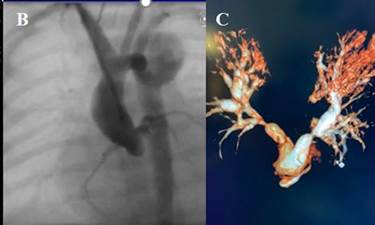

Fig.

1. Doppler echocardiography showing

critical aortic stenosis (A). Angiography through carotid access post

aortic valvuloplasty (B). Angiographic

reconstruction of surgical cerclage in both pulmonary

branches (C).

At 18 hours of life, combined cardiac catheterization

and aortic valvuloplasty with 6.0 × 20 mm Tylshak Mini hybrid balloon is performed through right

carotid access (dissection) (Figure 1B). On the fourth day the echocardiogram evidences 16

mm Hg peak transaortic gradient with mild aortic

regurgitation, and wide interatrial communication and

patent ductus.

life. Without clinical improvement, bilateral cerclage

with polytetrafluoroethylene (PTFE) band is performed

(Figure

1C) and the hybrid

procedure is completed 48 hours later (reopening of the sternotomy

and 1.7 mm Type E Krichenko stent implantation in the

ductus).